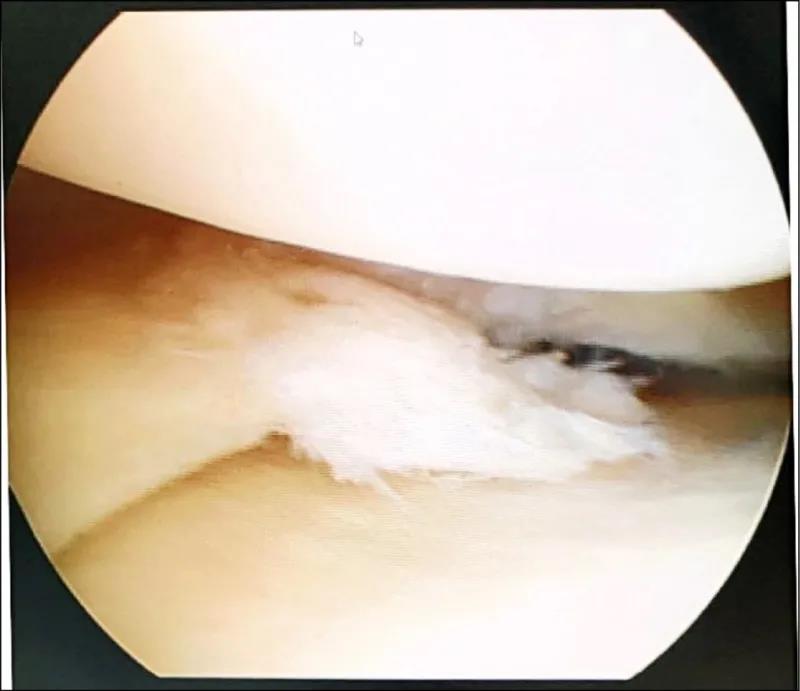

▲关节镜显示,半月板破裂处

理学检查发现,她的关节内侧明显压痛,建议做核磁共振(MRI)检查,才诊断出原来是膝盖半月板破裂,接受了关节镜微创手术后,慢慢回复正常生活。